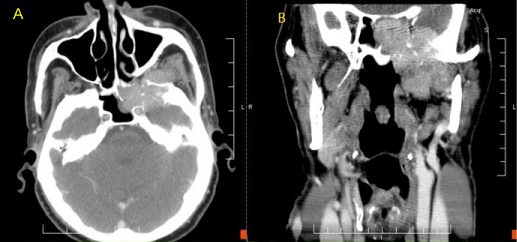

| Figure 1: CT Neck. A: Axial view. Mass in the left sphenoid sinus erodes through the intersinus septum, through the posterior ethmoid cells, and into the infratemporal fossa. B: Coronal view. Mass extends through the floor of the middle cranial fossa superiorly and into the infratemporal fossa inferiorly. |